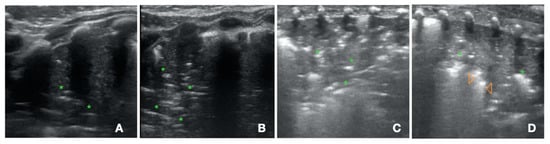

- A-Pattern (Figure 2A), normally aerated lung (aeration score = 0): A-lines, bilateral lung sliding (Video S2). The A-pattern in the absence of lung sliding suggests the presence of pneumothorax. In that case the lung point needs to be searched for. The lung point is point where the pneumothorax ends and the normal contact between the parietal and visceral pleura is restored. The corresponding ultrasound image is a scan where the a normal sliding is detected right aside a static pleura, representing the loss of contact between the parietal and visceral pleura. Therefore after the lung point, the pleural space is filled with air and the pleural sliding is absent (Video S3);

- B1-pattern (Figure 2B), moderate loss of lung aeration (aeration score = 1): three or more B-lines occupying less than 50% of the scanned area;

- B2-pattern (Figure 2C), severe loss of aeration (aeration score = 2): coalescent B-lines, occupying more than 50% of the scanned area;

- White lung (Figure 2D): compact B-lines that cause the acoustic shadow of the ribs to disappear within the entire scanning zone, anteriorly and posteriorly without spared areas;